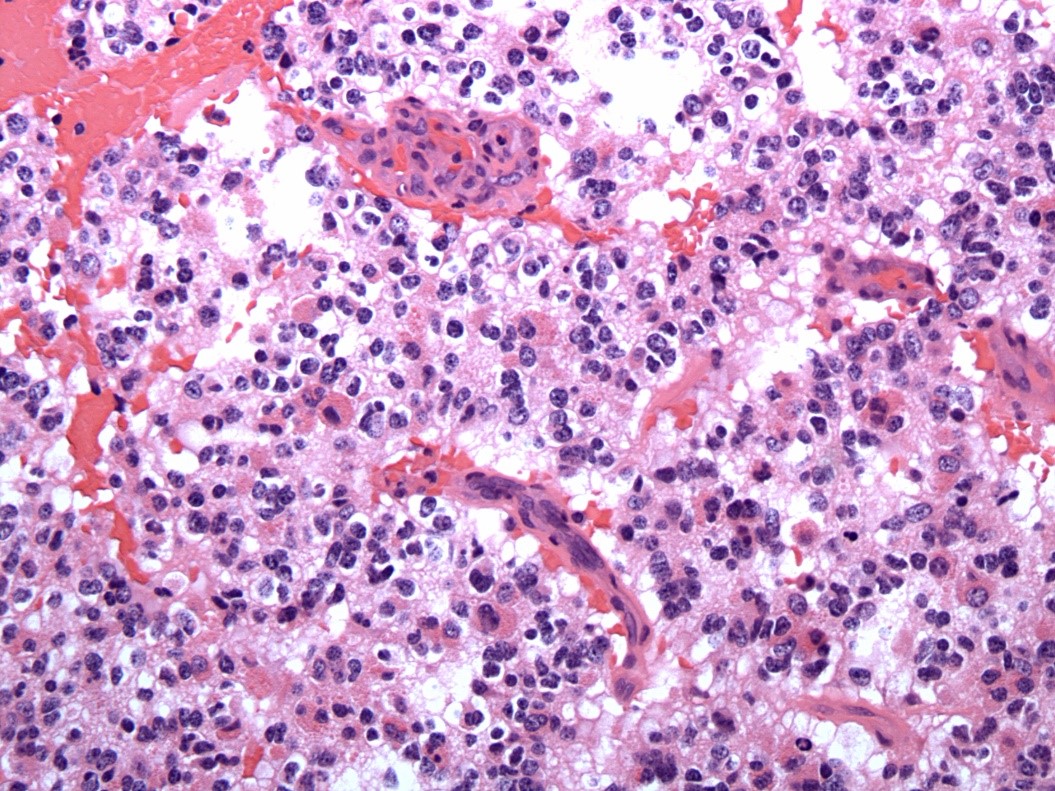

40 year old male found unresponsive. No medical or social history. The scene was unremarkable. External examination revealed scars on the forearms and legs. Autopsy revealed 450 g heart, edematous lungs, and firm liver.